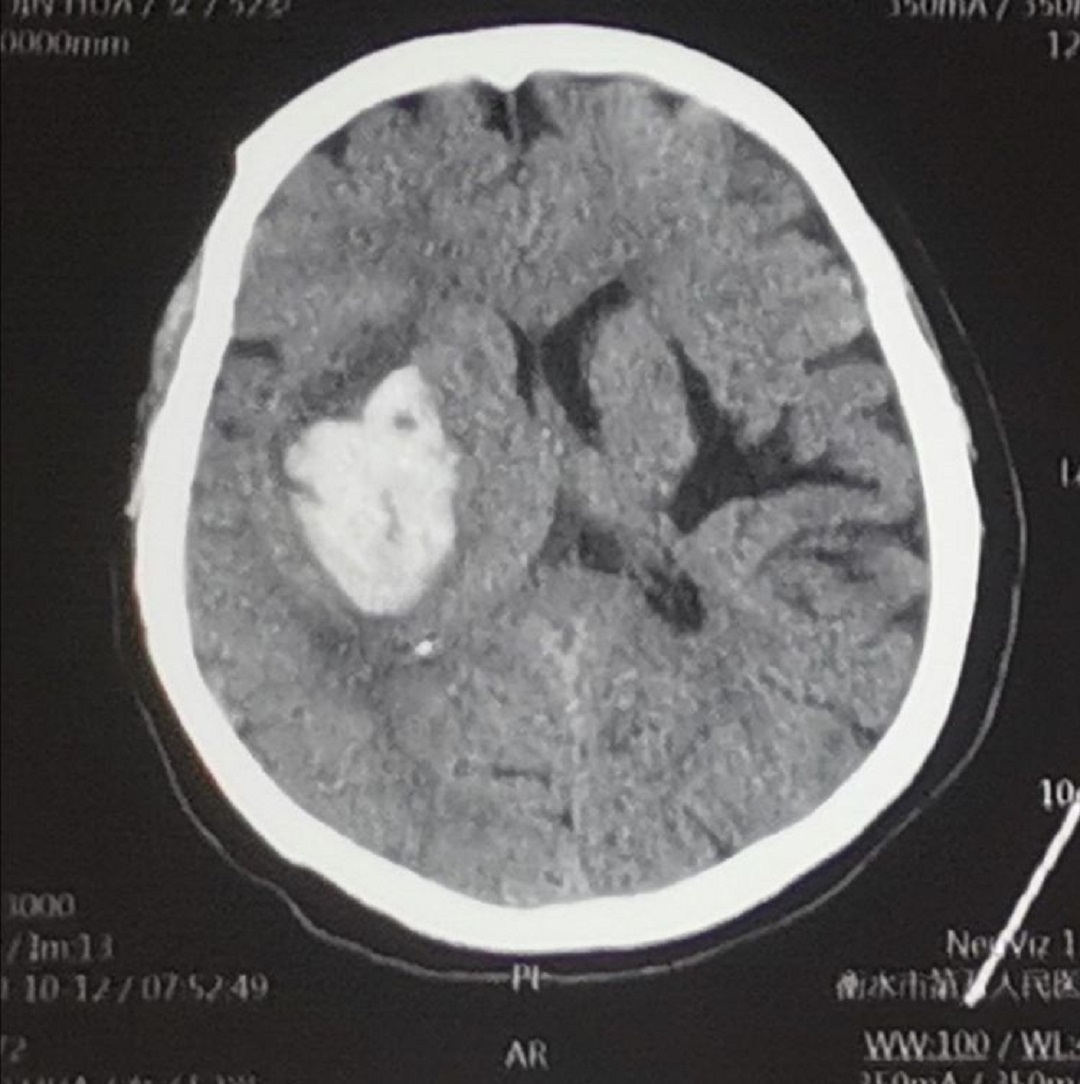

患者李xx,女,52歲,主因突發(fā)意識障礙伴左側(cè)肢體活動障礙1小時急診入院,查體:生命體征穩(wěn)定,昏迷狀態(tài),刺激略有睜眼,不發(fā)音,雙側(cè)瞳孔正大等圓,對光反射靈敏,刺痛肢體略屈曲,雙側(cè)巴氏征陽性,頭部CT平掃提示:右側(cè)基底節(jié)區(qū)腦出血。入院診斷:1.右側(cè)基底節(jié)區(qū)腦出血,2.高血壓3級,很高危。

術(shù)前CT